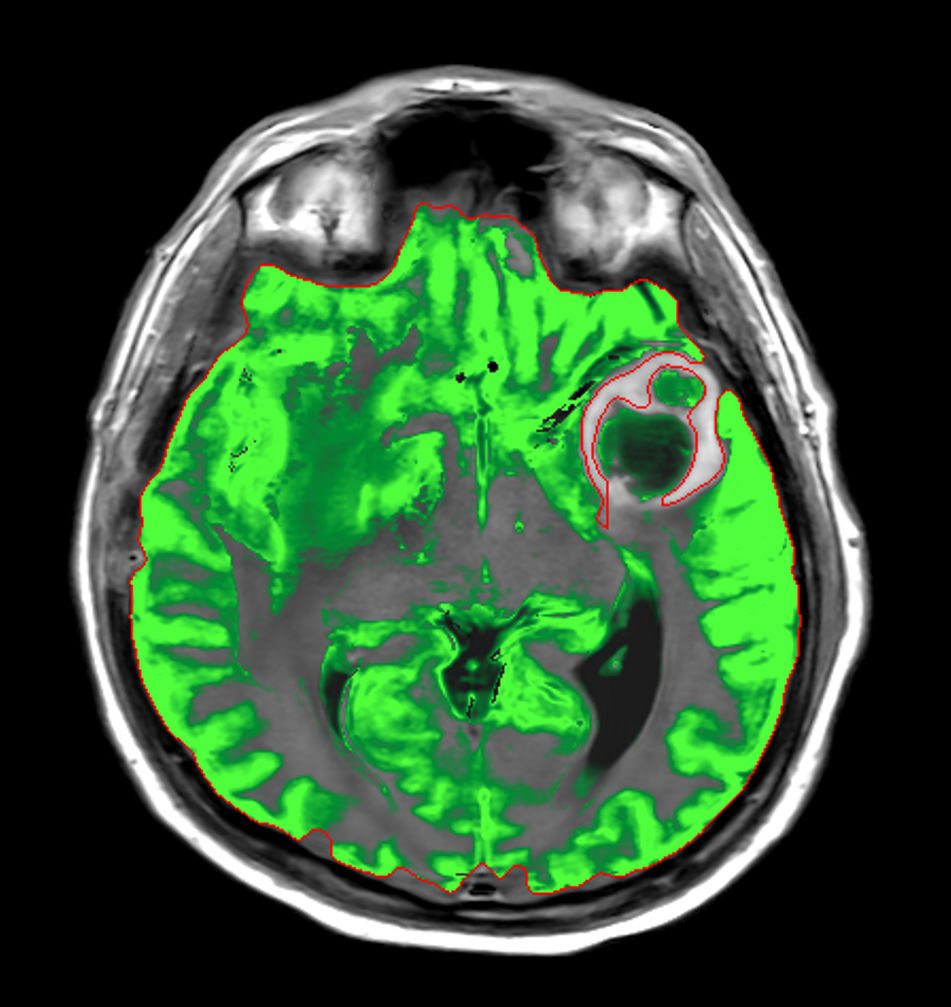

Patient with a large brain lesion. AI based SmartSpeed is utlized to shorten scan time without compromise in image quality. Advanced imaging techniques like pCASL and 3D APT are used to perform contrast-free brain imaging to assess perfusion and tumoral activity. SWIp 3D susceptibility weighted offers the high sensitivity required to visualize deoxygenated (venous) blood or calcium deposits. A single synthetic (SyntAc) brain quantification scan is added. The resulting data of this scan can be used as input for advanced third party processing software* to synthesize MR images with different contrasts, brain parenchyma fraction maps and/or brain segmentation maps.

Axial SyntAc (Grey Matter)

Axial SyntAc (White Matter)

Axial SyntAc (CSF)

Axial SyntAc (No GM, WM, CSF)